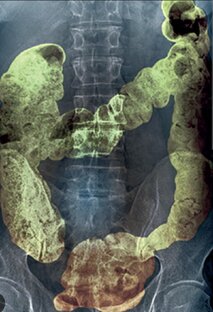

Что необходимо знать о задержках стула❓ Кроме того, что ЗАПОР это всегда ДОСАДНО, нередко МУЧИТЕЛЬНО, а порой и ОПАСНО ⤵

Все самое важное из серии моих видео о нарушениях дефекации я собрал в эту статью для тех, кому удобнее найти все актуальное по этой теме в одном общем тексте. Если вы уже знакомы с моими видео на данную тему вам, возможно, тоже будет удобно пользоваться общим текстом и обращаться по необходимости к отдельным роликам, ссылки на которые размещены в соответствующих разделах этой статьи. Для большего удобства пользуйтесь оглавлением (если платформа, на которой он размещен будет поддерживать эту функцию)...